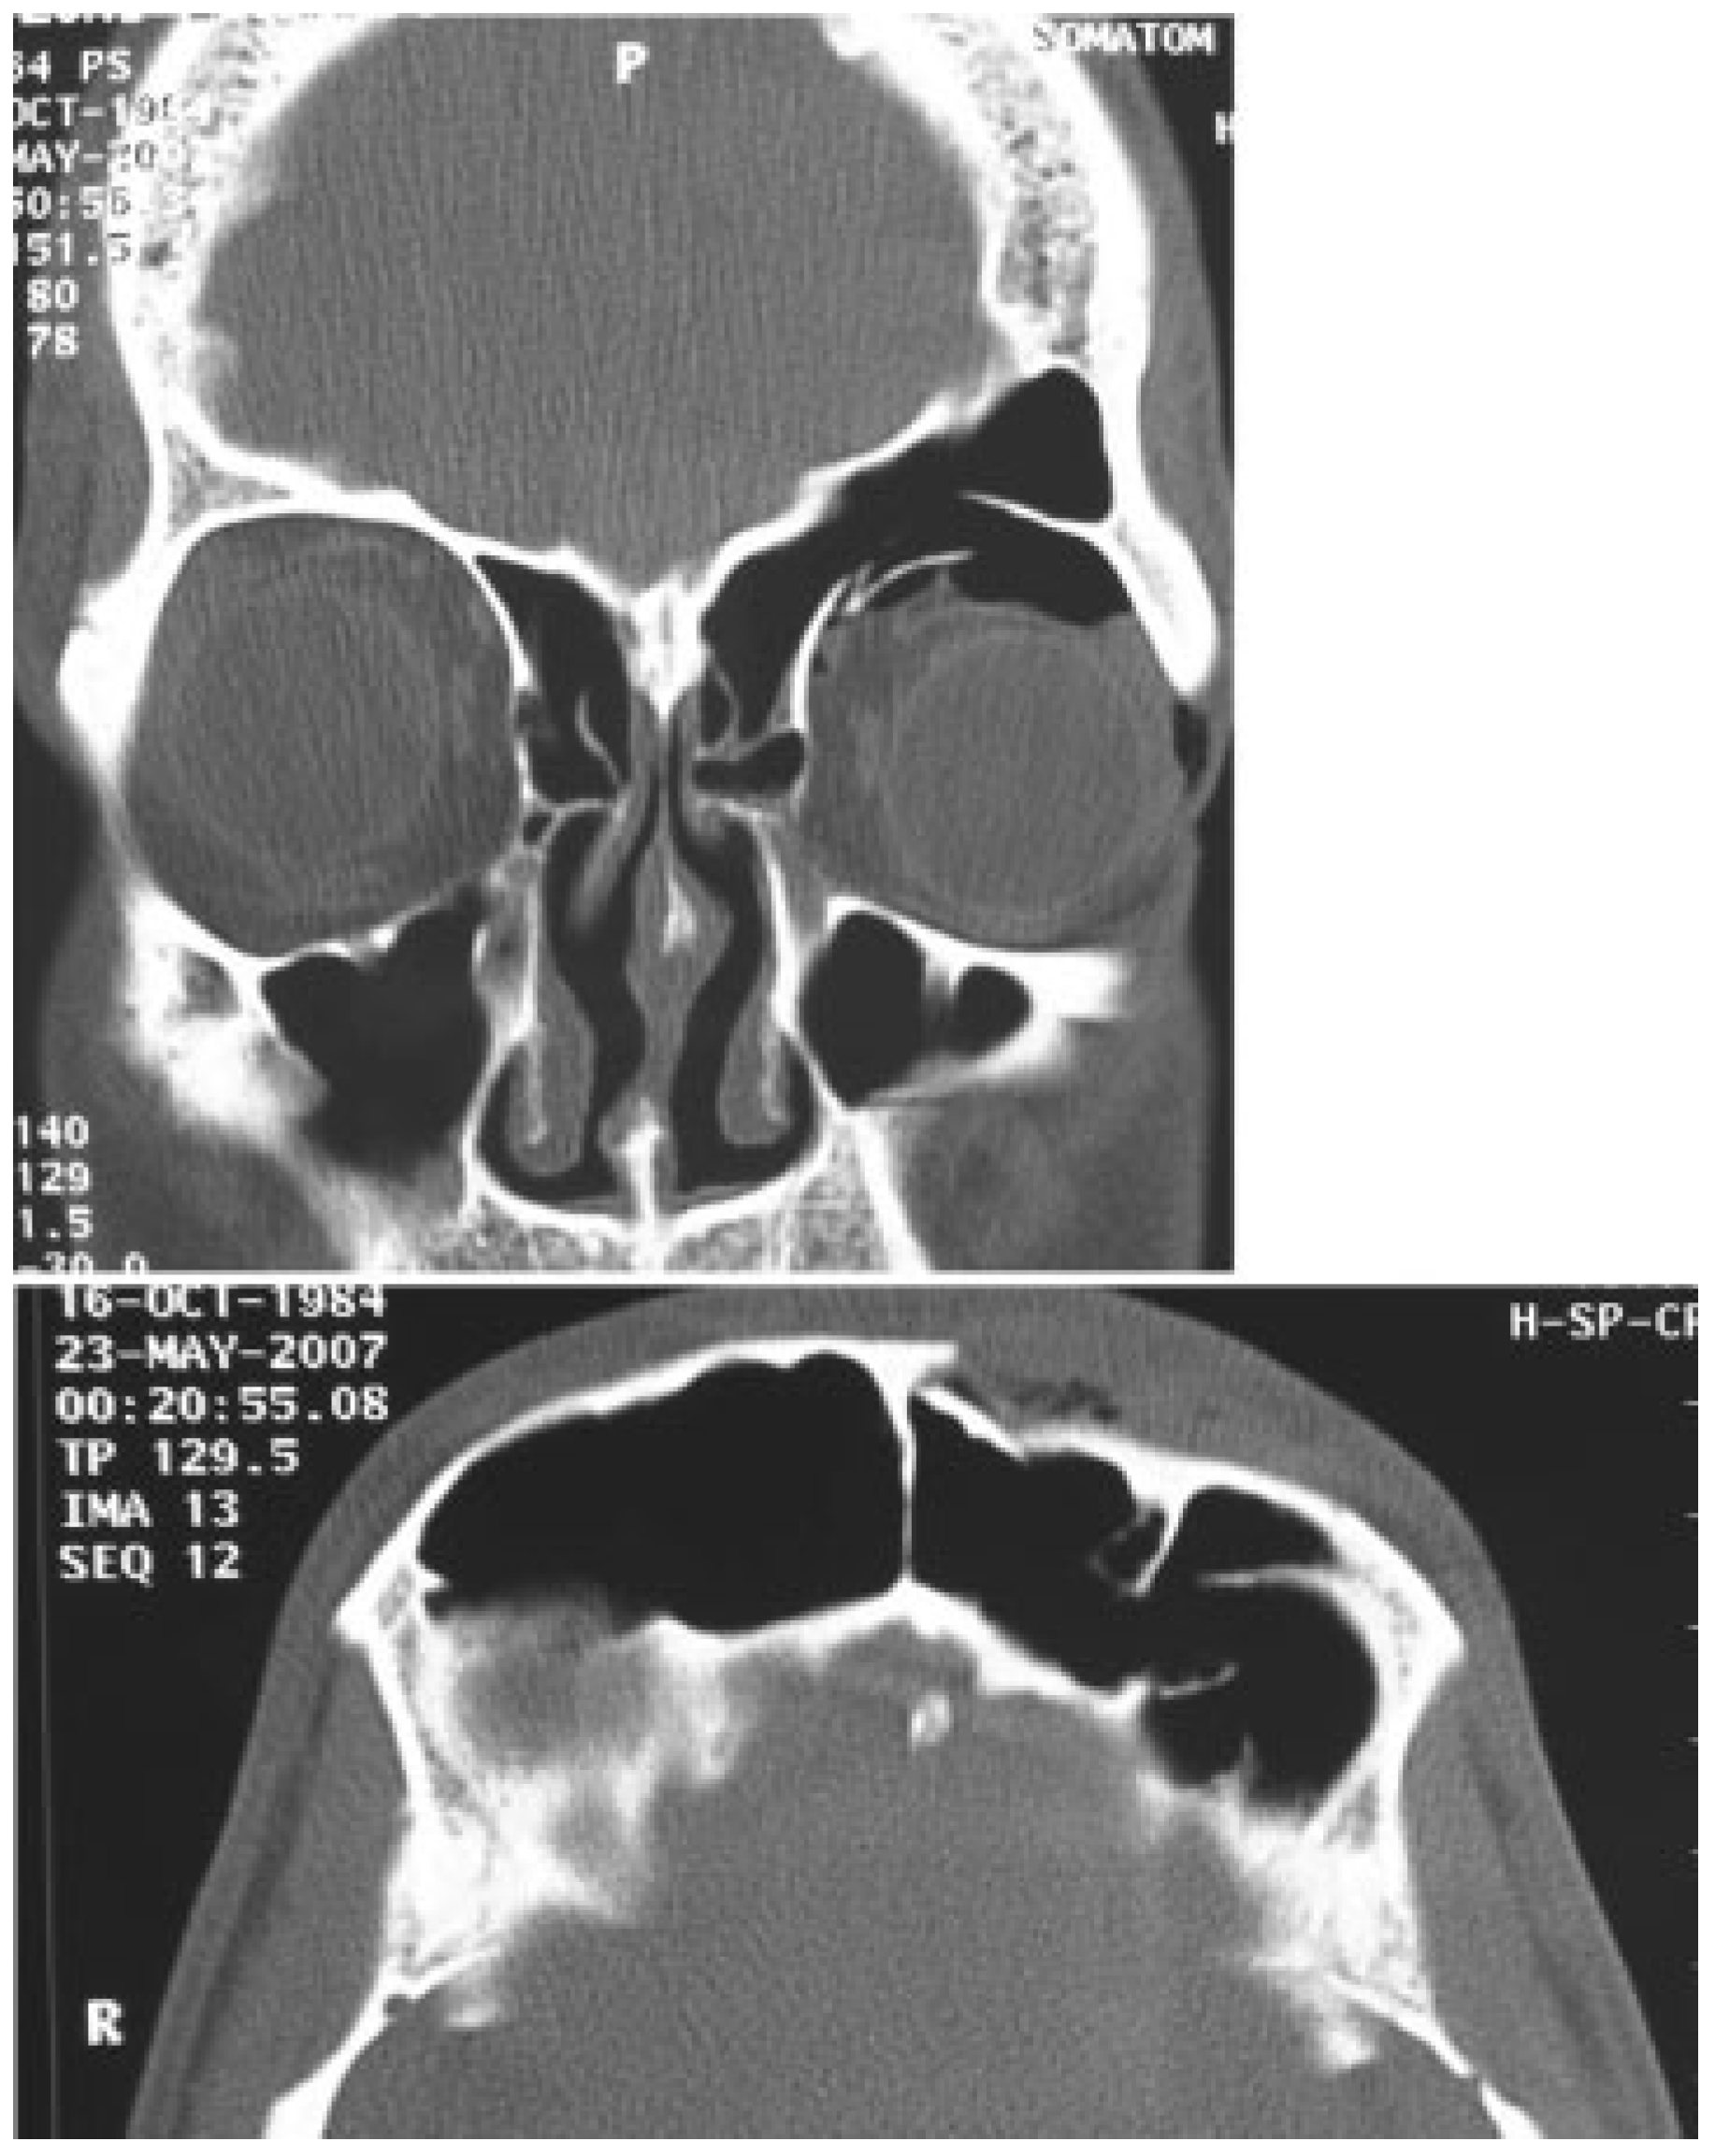

A 22-year-old man was referred to our department for a craniofacial trauma caused by a sport accident. The patient presented a visible and palpable frontal bone depression, periorbital ecchymosis, and eyelid ptosis (Figure 1). A computed tomography (CT) scan showed displaced frontal sinus anterior table fracture associated with orbital roof fracture with intact nasofrontal drainage system (Figure 2). The fractures were treated through a unilateral zigzag pretrichial incision exposing a wide surgical field allowing open reduction and internal rigid fixation (Figure 3). A postoperative CT scan showed a good restored bone contour (Figure 4). Surgical incision healed without complications (Figure 5), and after 20 months of follow-up, scar is quasi invisible (Figure 6).

Figure 4. Postoperative coronal and axial computed tomography images.